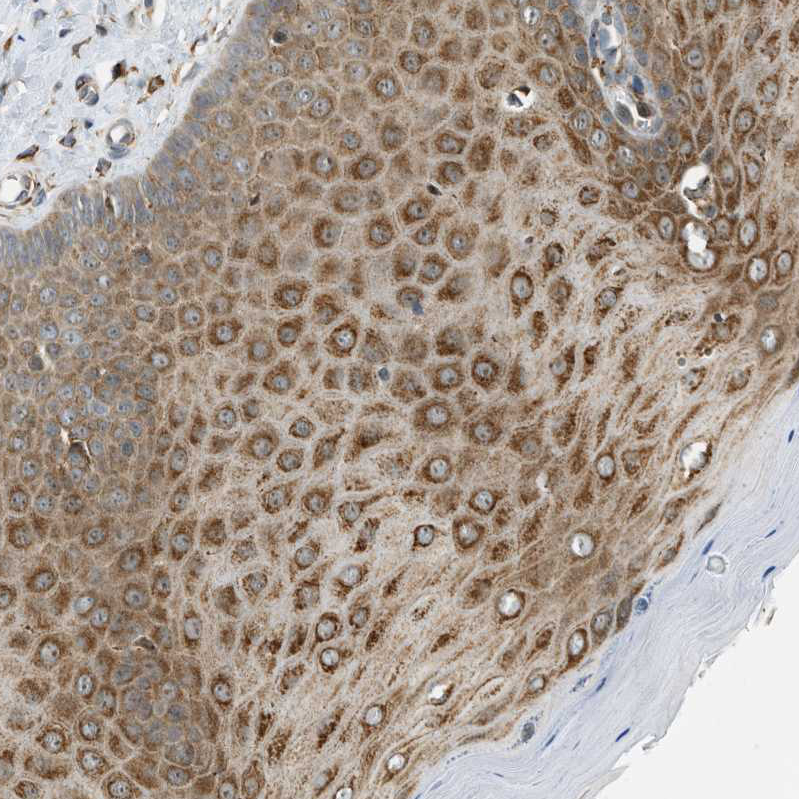

Semaphorin-4D (SEMA4D) also known as Cluster of Differentiation 100 (CD100), is a protein of the semaphorin family that in humans is encoded by the SEMA4D gene.

Semaphorin 4D (Sema 4D) is an axon guidance molecule which is secreted by oligodendrocytes and induces growth cone collapse in the central nervous system. By binding plexin B1 receptor it functions as an R-Ras GTPase-activating protein (GAP) and repels axon growth cones in both the mature central nervous system.

In the immune system, CD100 binds CD72 to activate B cells and dendritic cells, though much about this interaction is still under investigation.

During skin damage repairs, SEMA4D interacts with Plexin B2 on Gamma delta T cells to play a role in the healing process.